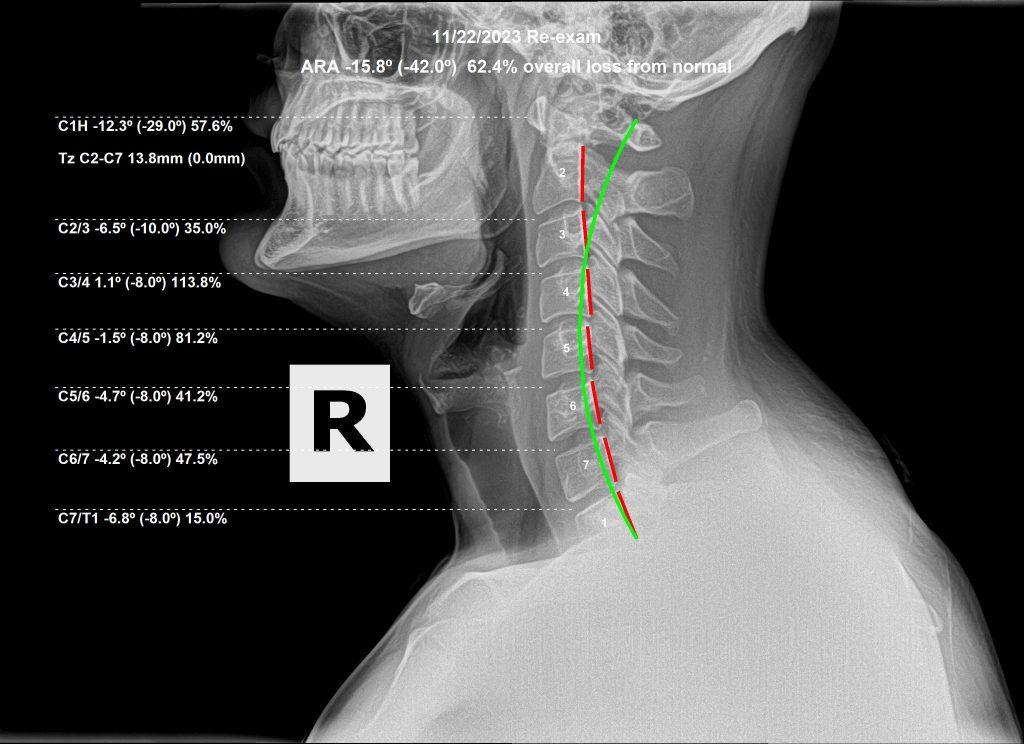

Lateral cervical X-ray after spinal correction

Lateral View — After Care

A 27-year-old male suffered a gym injury to his neck, presenting with headaches, double vision from a newly developed lazy left eye, facial pain and paresthesias, and paresthesias radiating into his arms. After 3 months of care, all symptoms had resolved — including the lazy eye. He was even showing signs of holding his adjustments.

And then a series of high-stress life events occurred. He began having low back pain (which he had never complained of before), his upper back posture appeared to be worsening, and he started experiencing ankle pain and discomfort.

Structural correction is important. We expect to see spinal change in the proper direction over time. But the most important thing is that functional improvement occurs. By the grace of God, and the innate intelligence of the body, whenever we correct subluxations, function will be restored and improved. We will always move in the right direction. It is possible — and normal — to be better and worse at the same time.